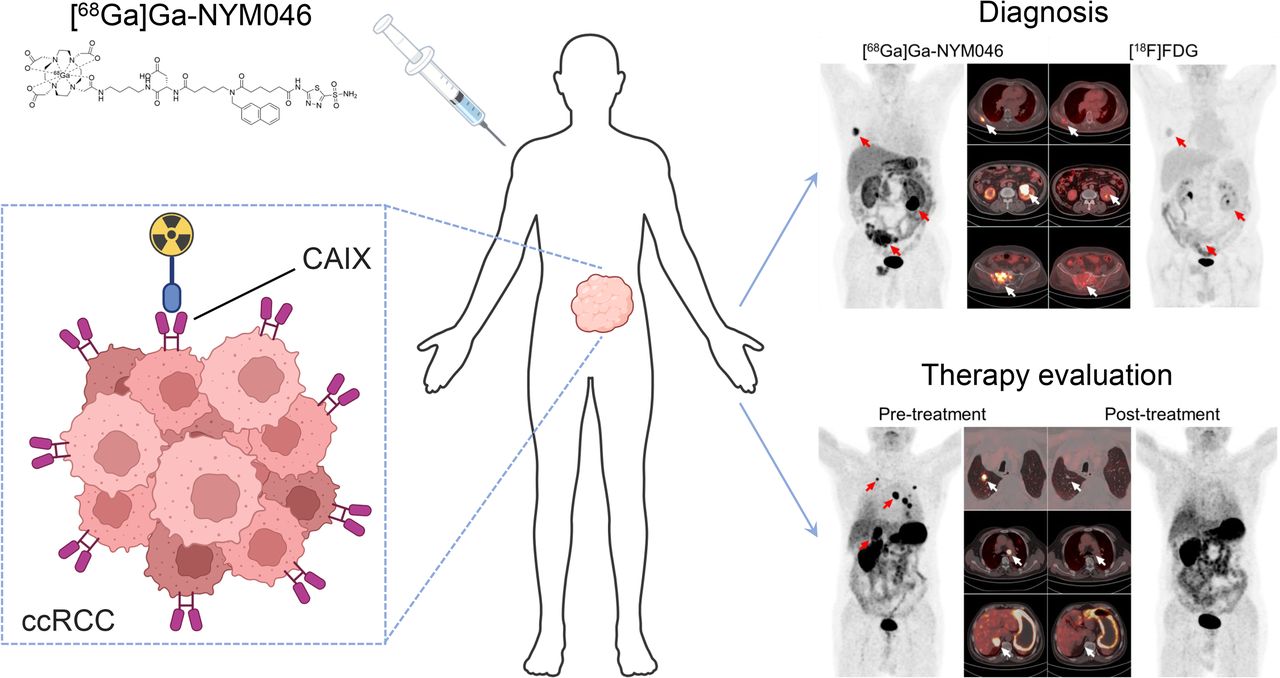

Molecular Imaging for Integrat Tamaki, Nagara; Kuge, Yuji 18F-Fluorodeoxyglucose Imaging for Assessing Cardiovascularの詳細情報

18F-Fluorodeoxyglucose Imaging for Assessing Cardiovascular。Imaging of C-X-C Motif Chemokine Receptor 4 Expression in。Synthesis, preclinical, and initial clinical evaluation of。

MolecularImagingforIntegrat

MolecularImagingforIntegrat